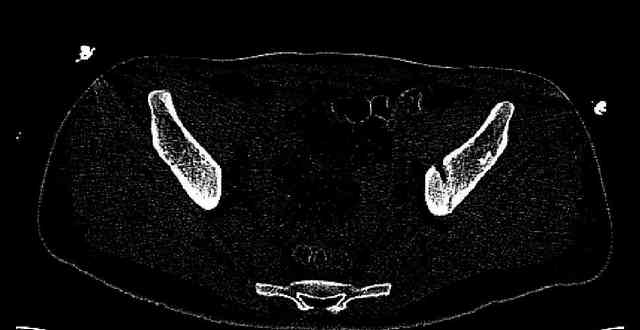

Some more images. Does it help to guess which part of the acetabulum is displaced?

Normal appearing SI joints and a healed posterior column limb... my bet's on caudal segment displacement.

The anterior element of the fracture is so low and the anterior roof arc angle must be at least 60 deg.

The posterior element is so minmally undisplaced. There is good congruence of the joint, and to top it all, 6 weeks have passed. If you consider ORIF now, I don't expect that much improvement could be accomplished. Not to mention the need for extensive approaches with their morbidity.

If you leave him alone now, and if the need arises in the future I believe that a standard THR would be good enough. And this is of course a much simpler procedure than the ORIF currently considered.